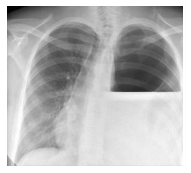

Após cerca de 30 minutos, o paciente

apresentado na questão anterior evolui com

PA 90X60 mmHg, FC 139bpm e turgência

jugular. As bulhas eram normais e o

murmúrio vesicular reduzido à esquerda.

Estava pálido, sudoreico e com extremidades

frias. Havia acabado de realizar a seguinte

radiografia de tórax:

Com base no exposto, qual é a etiologia mais provável para o choque e qual é a conduta adequada?